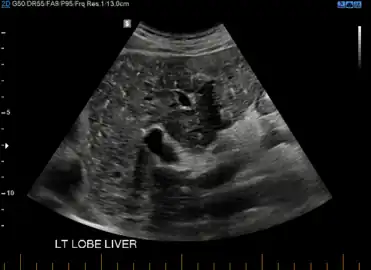

von Meyenburg Complex in ultrasound. Numerous little cysts with ringdown artefacts.